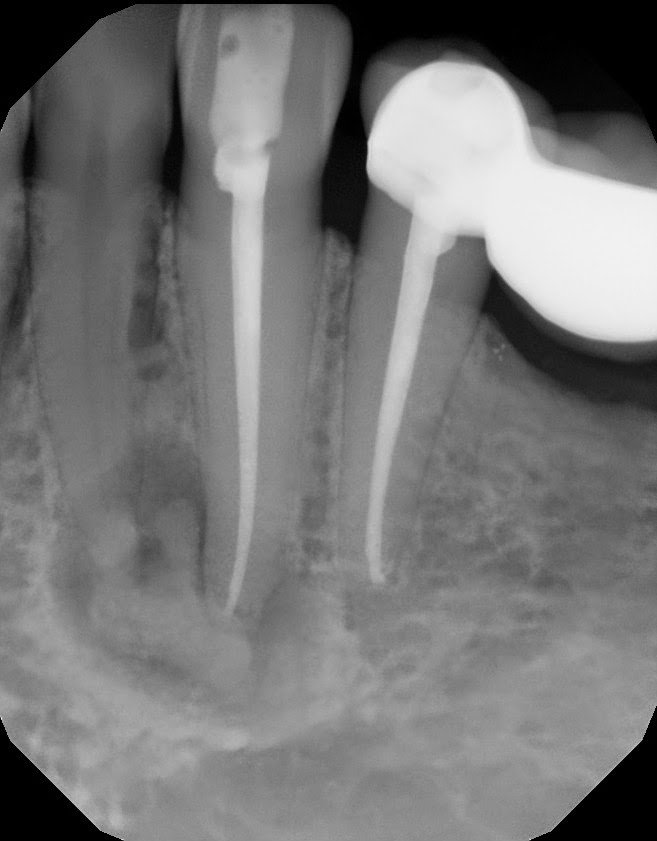

A 42 yr old, white, female presented for evaluation of #22. She was asymptomatic, with a prior RCT on #22. A large nodular, irregular, radiopacity found within a large radiolucent area on the periapical radiograph. Tooth is normal to palpation, percussion and probings.

DX: Prior RCT with possible periapical cemental dysplasia. Apical surgery recommended with biopsy.

Biopsy report indicated Periapical Cemental Dysplasia (anterior focal osseous dysplasia) Recurrence would be unusual, but other areas of dysplasia can arise as well as truamatic bone cysts are also common.